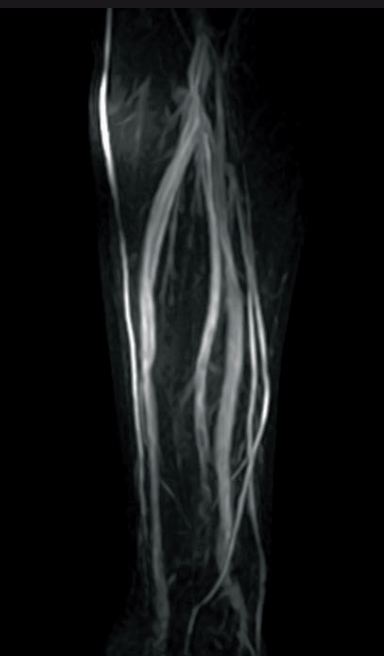

Respiratory-gated MIP image